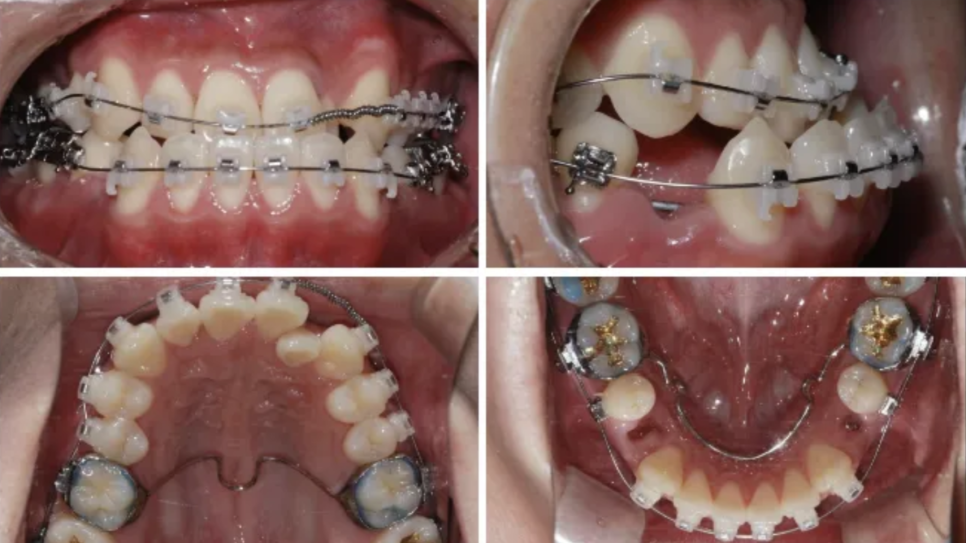

As a result of the diagnosis, the teeth were unevenly positioned due to insufficient space,

and because of mandibular overgrowth, the lower front teeth protruded beyond the upper front teeth.

After a detailed analysis of the patient’s facial features, X-rays, and dental arches,

we expanded the shape of the upper and lower arches,

This is what it looks like while wearing the arch expansion device

and performed tooth extraction for backward movement of the lower jaw, moving the lower front teeth backward.

In this process, we also precisely adjusted the occlusion so that the temporomandibular joint would not be strained.

Around 12 months later, the extraction spaces had closed, and you can see that the teeth were moving inward well.